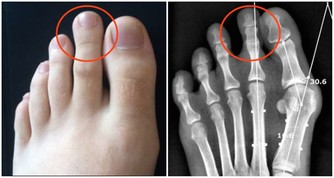

3、蒼白

貧血,白血病,心臟疾病和雷諾嚴重障礙現象都可以引起蒼白。

此外,壓力,體力消耗,長期暴露在陽光和遺傳變異也是

導致臉色蒼白的原因,這是一個循環不良症狀。

白斑,白指甲,色素沉著也與血液循環不暢有關。